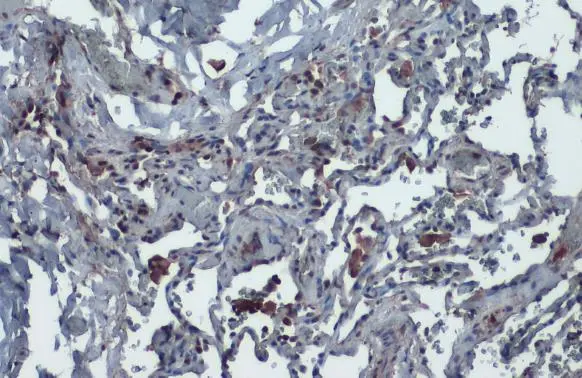

![Anti-ACE2 antibody [N1N2], N-term used in IHC (Paraffin sections) (IHC-P). GTX101395](/upload/website/prouct_img/middle/GTX101395/GTX101395_20240411_citeab_IHC-P_227_24041501_257.webp)

The data was published in the 2022 in Biomedicines. PMID: 35625919